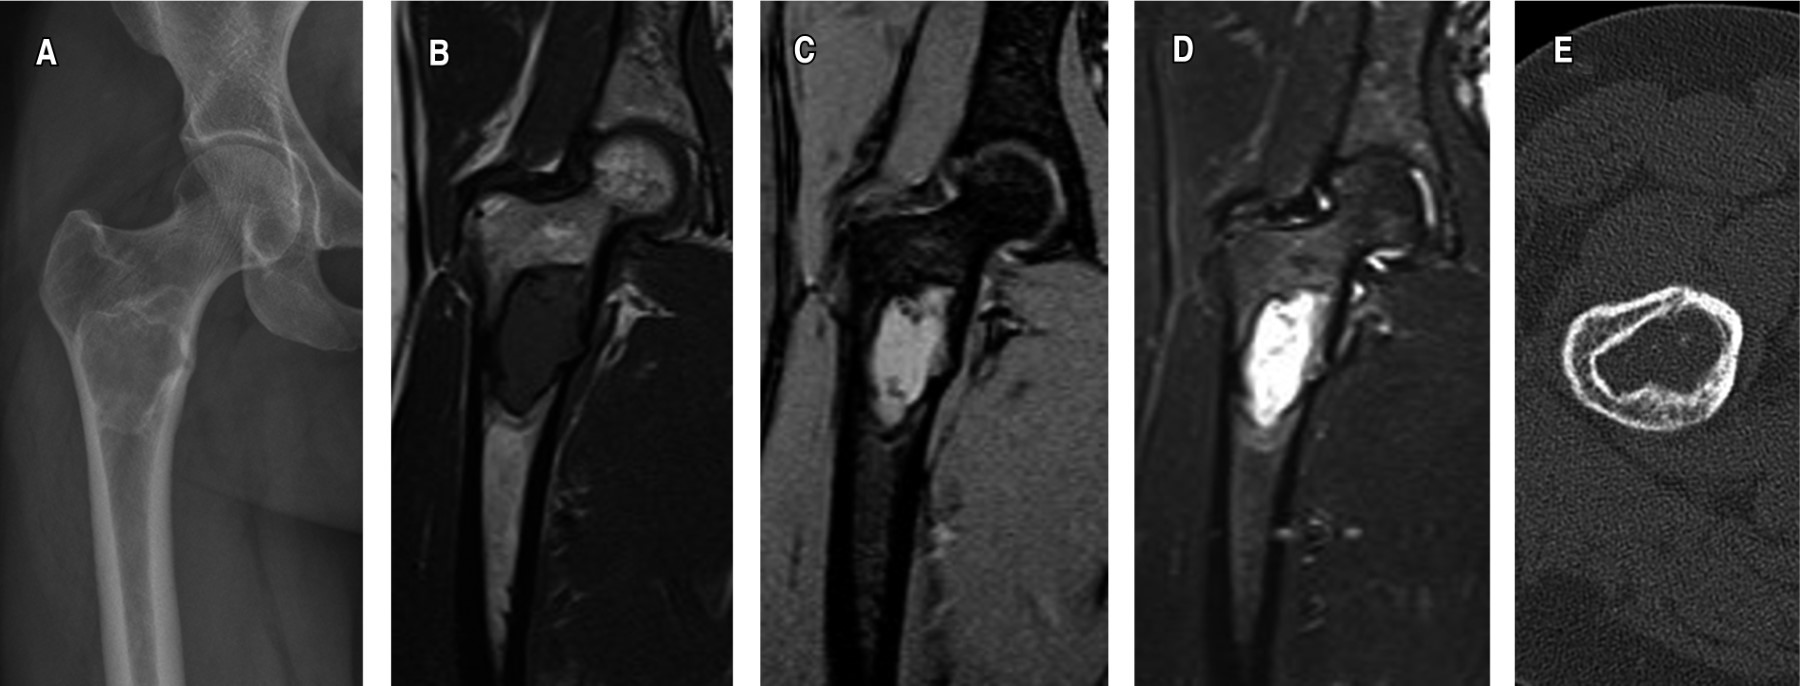

Figure 2